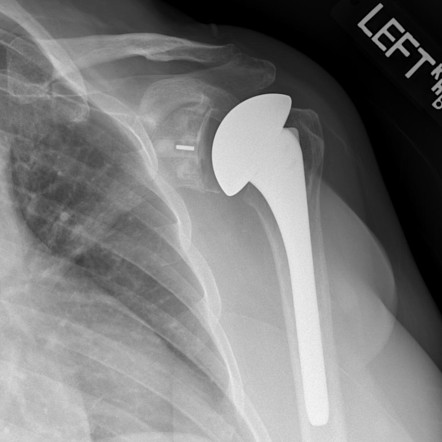

- A metal ball (replacing the humeral head) and a plastic socket (replacing the glenoid surface) are implanted to restore smooth motion.